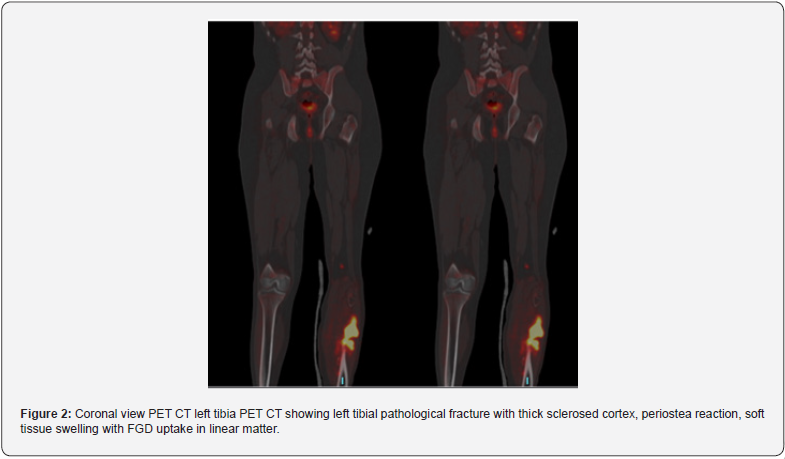

Primary osseus malignant lesions were detected in 11 patients (22%) (Figure 1) and osseous benign lesions were detected in 6 patients (12%) (Figure 2). Out of 31 extra osseus malignant primary lesions, 9 was prostatic acinar adenocarcinoma, 4 invasive ductal carcinoma of the breast, 1 mastitis carcinomatosis, 5 pulmonary adenocarcinoma, 1 squamous cell carcinoma of the lung, 2 adrenocortical carcinoma, 1 papillary and 2 clear cell renal carcinoma, 2 hepatocellular carcinoma, 1 epithelial cell carcinoma of the ovary, 1 undifferentiated pleomorphic lesions of sarcoma and 1 mesothelioma of the pleura (Figures 1 & 2).